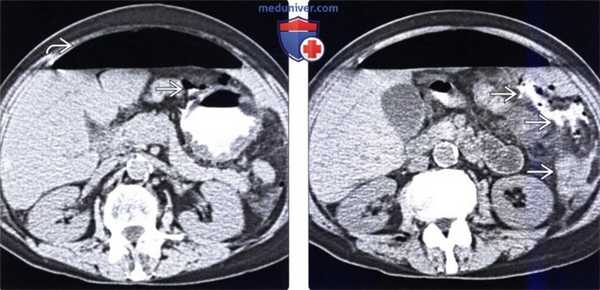

(Слева) При нативной КТ, показанием к которой послужила перфорация язвы желудка, визуализируется утолщенная стенка желудка и большое количество свободного газа в полости брюшины. Внепросветный контраст и газ определяются также возле передней поверхности желудка, что отражает наличие перфоративной язвы.

(Справа) У этого же пациента имеются признаки выхода контрастного вещества за пределы желудка, а в результате смешивания контраста с асцитической жидкостью она становится гиперденсной. Обратите внимание, что язва желудка может открываться в малый брюшинный мешок либо в основную полость брюшины, как и произошло в этом случае.